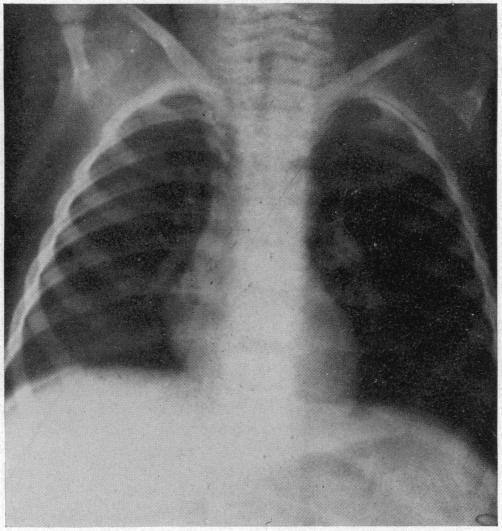

ACUTE MASSIVE COLLAPSE OF THE LUNGS: A DISCUSSION OF ITS MECHANISM AND OF ITS RELATION TO FOREIGN BODIES IN THE BRONCHI AND POST-OPERATIVE COMPLICATIONS.

Ann Surg. 1925 Sep;82(3):364-89. doi: 10.1097/00000658-192509010-00005.